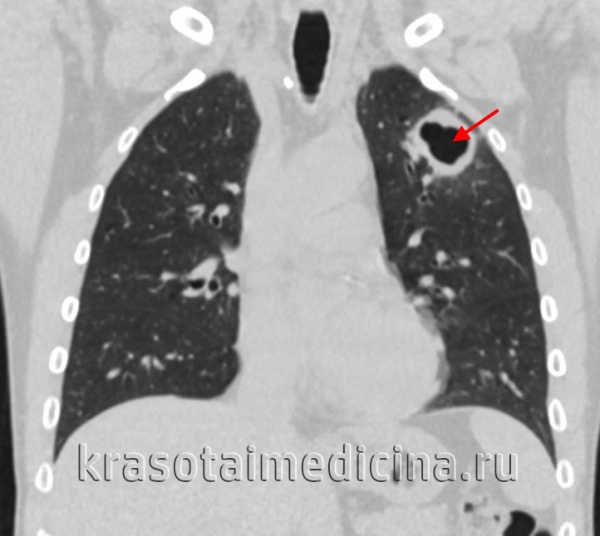

- Лучевая диагностика.Рентгенография легких является обязательным диагностической процедурой, позволяющей выявить характер изменений в легочной ткани (инфильтративный, очаговый, кавернозный, диссеминированный и т. д.), определить локализацию и распространенность патологического процесса. Выявление кальцинированных очагов указывает на ранее перенесенный туберкулезный процесс и требует уточнения данных с помощью КТ или МРТ легких.